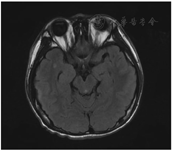

入院查体:体温37.2 ℃,脉搏80次/min,呼吸22次/min,血压90/60 mmHg(1 mmHg=0.133 kPa),意识清,精神可,营养良好,发育正常,自动体位。周身皮肤黏膜无黄染、皮疹及出血点,浅表淋巴结不大,头颅无畸形。双侧瞳孔等大等圆,对光反射灵敏,颈软无抵抗,双肺及心脏检查正常。神经系统检查:浅感觉正常,深感觉检查不配合,复合感觉检查不配合,浅反射正常,肱二头肌反射正常,双侧膝、跟腱反射正常,生理反射存在,病理反射未引出,双侧巴氏征阴性、克氏征阴性、布氏征阴性。辅助检查:血常规示白细胞计数2.9×106/L;中性粒细胞% 46.1%;淋巴细胞% 36.3%;单核细胞% 16.2%;红细胞计数5.05×1012/L;血小板计数89×109/L;血清淀粉样蛋白A 120.09 mg/L;全血C-反应蛋白4.83 mg/L。脑电图正常,头颅MRI平扫示小缺血灶,脑炎不除外(图1)。完善头部MRI检查后患儿突然出现头痛剧烈,手脚发麻,四肢颤抖,深大呼吸,情绪激动,无明显意识障碍及喷射样呕吐。初步诊断考虑重症病毒感染,中枢神经系统感染不除外。入院第2天行腰椎穿刺检查,颅内压约80 mmH2O(1 mmH2O=9.81 kPa),脑脊液常规:潘氏试验弱阳性,红细胞计数1×106/L;脑脊液生化:蛋白442 mg/L,糖2.66 mmol/L,氯119.3 mmol/L均在正常范围内,同时留取血液及脑脊液。为确定感染原,经医学伦理审核及家长签字同意后,对留存的血液和脑脊液样本进行病原微生物mNGS检测,均显示HPVB19阳性,诊断为病毒性脑炎,见表1。

右侧颞叶皮质下可见一小斑片状T2高信号,T2FLAIR呈高信号,弥散像信号不高,余脑质形态信号正常,脑炎不能完全除外。